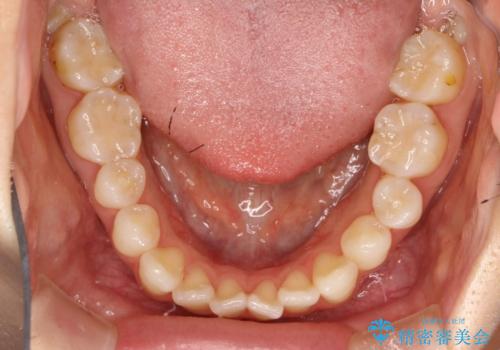

軽度の前歯のガタガタをインビザラインでの目立たない矯正

- 前歯のガタガタを主訴に来院されました。

軽度であったため、枚数制限のあるタイプのインビザラインのプランで治療することとしました。

軽度のガタガタを目立たずに手軽に矯正できるのもマウスピース矯正の魅力といえます。